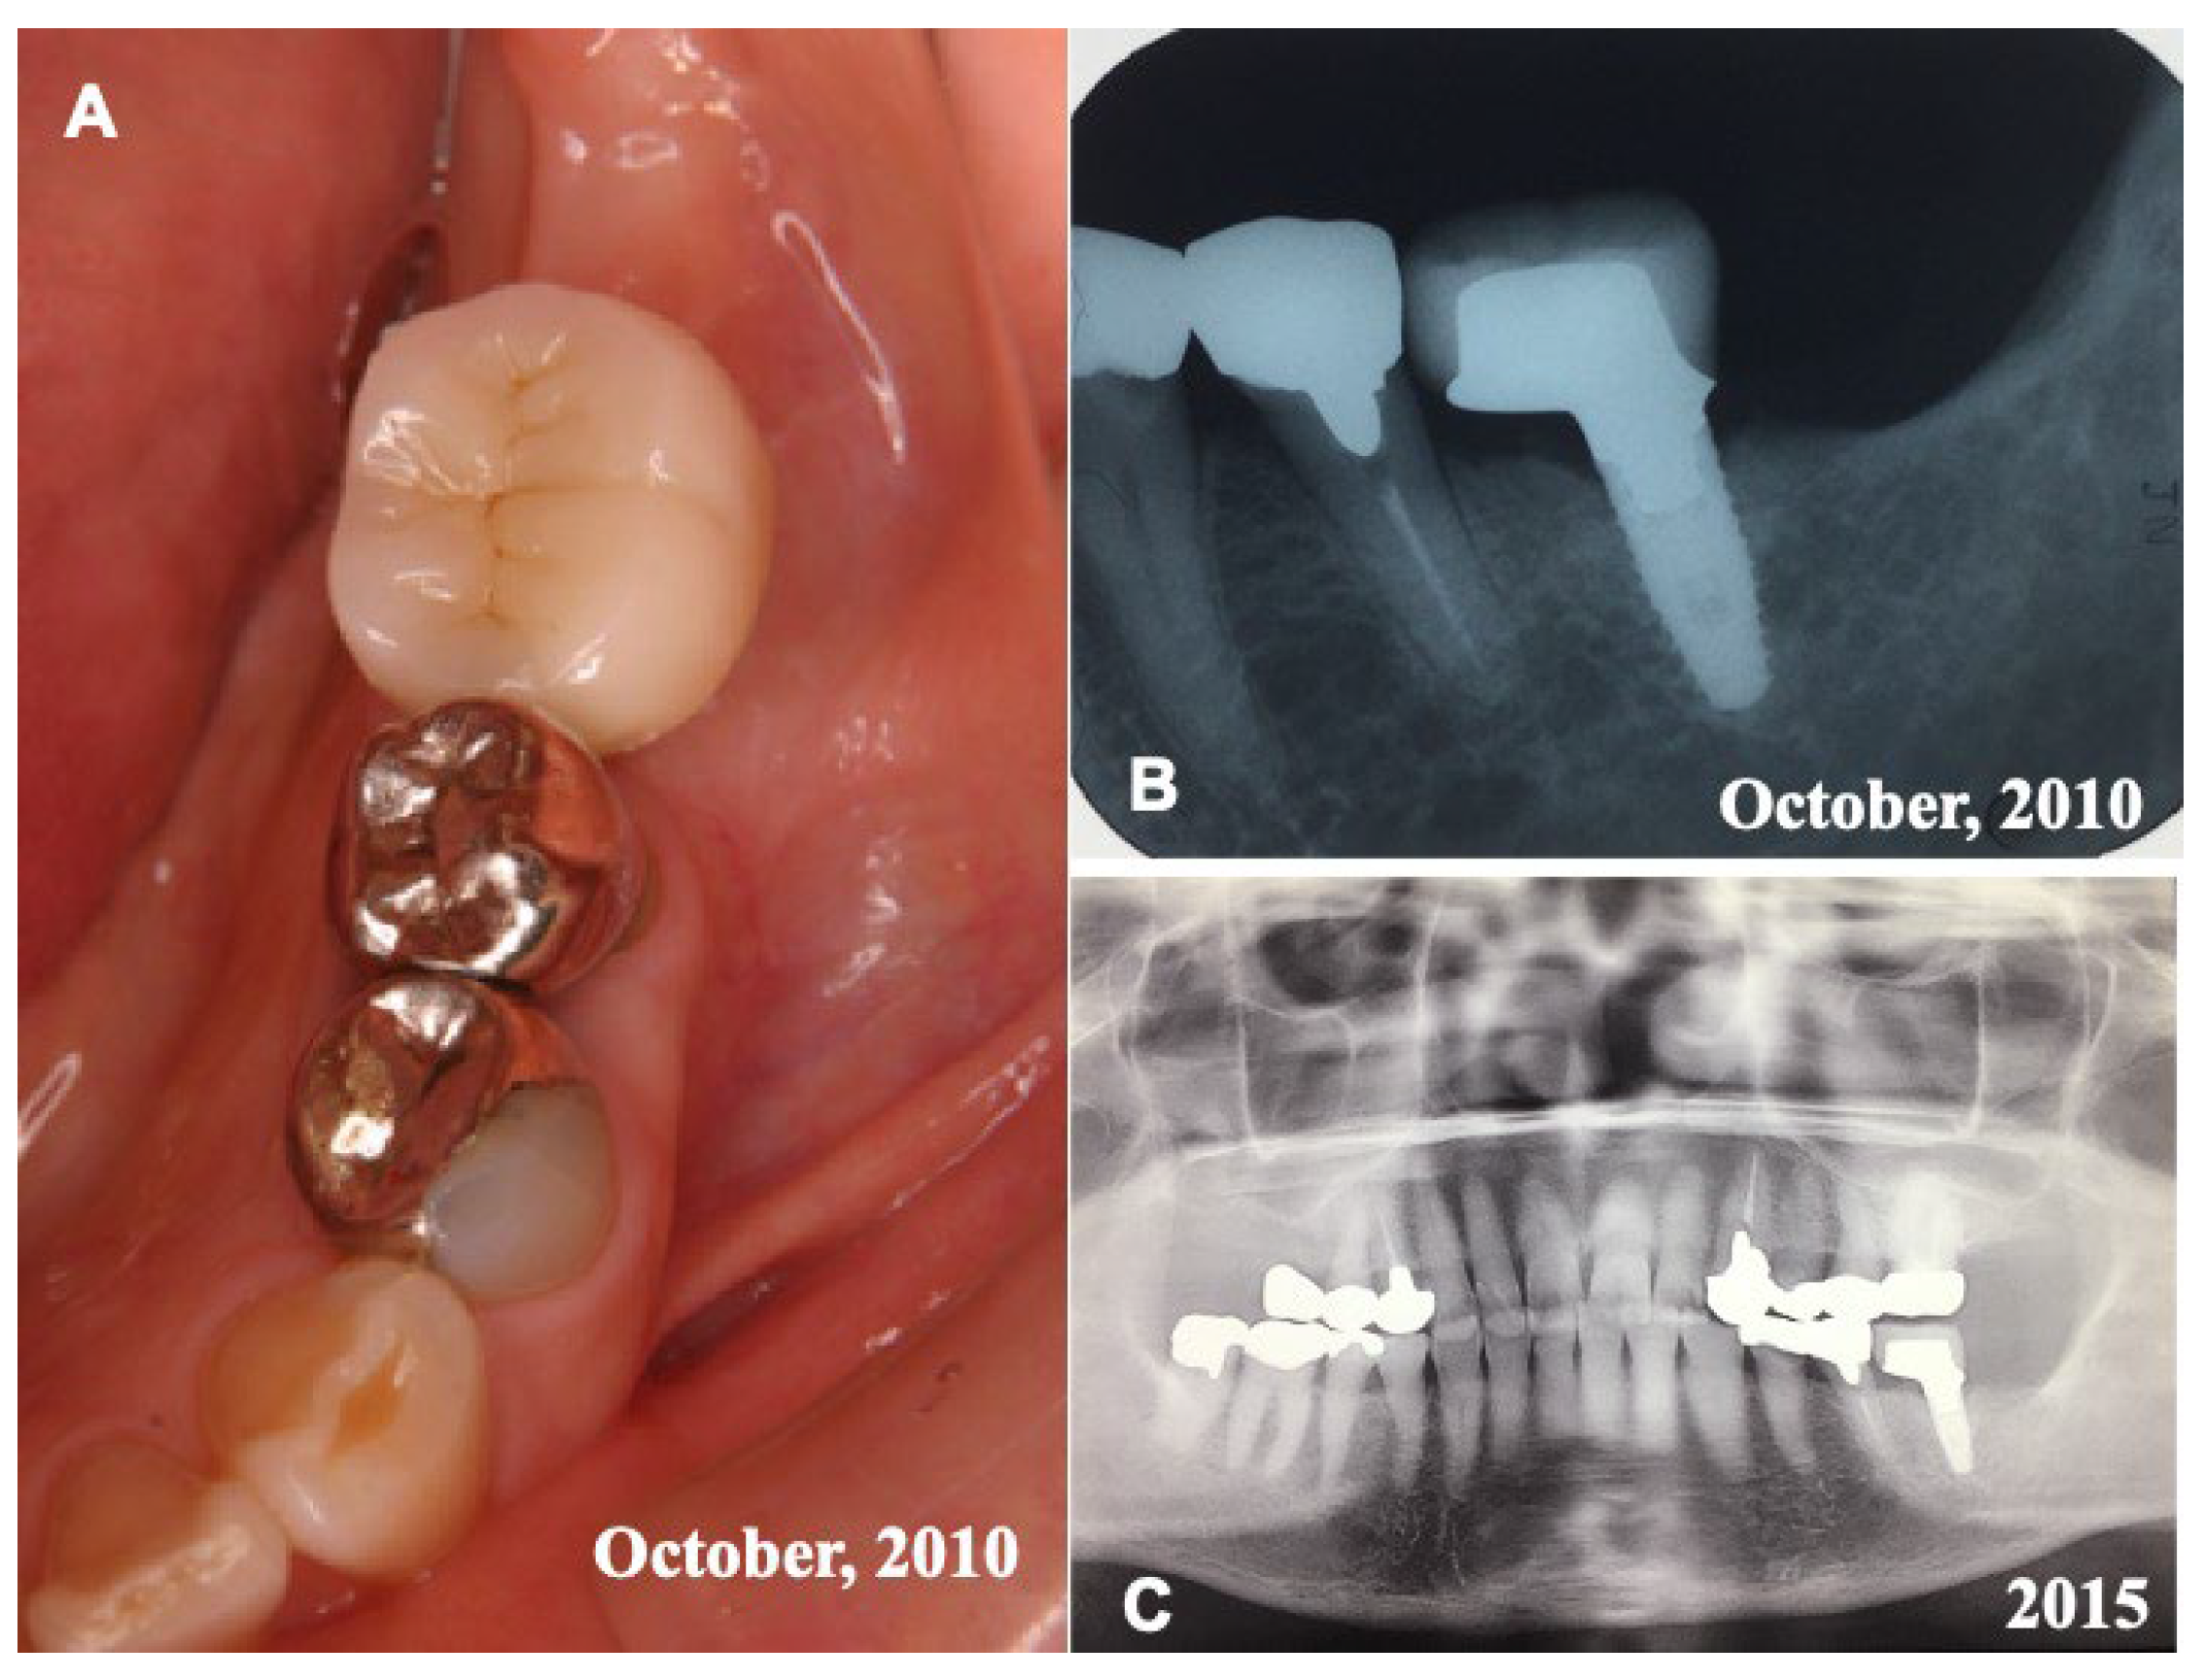

Before the pDDM graft (Surgery 1), the lamina dura (#36) remained clear. (Figure 1A,C). Just after the pDDM graft, pDDM were seen like radio-opaque granules in the treated socket (Figure 3D). At 5 months (Surgery 2), a smooth surface line was seen on the graft site after the opening of mucoperiosteal flap (Figure 4A). The grafted pDDM was harmonized with the mandible, and a bone-like radio-opacity was found in the graft region (Figure 4B). A titanium-fixture was placed properly after the biopsy (Figure 4C,D). The final crown was set (Figure 5A,B) and functionality was well maintained. During the whole follow-up period, a complication, such as marginal bone loss, did not occur (Figure 5C).

Figure 5.

Final crown and X-ray photos. (A) Set of final resin crown in 2010. (B) X-ray photo in 2010 showing fixture with crown. (C) X-ray photo in 2015 showing good appearance at 6 years after placement of fixture.